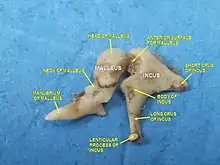

L'enclume ou incus[1] est un des trois osselets de l'ouïe situé dans l’oreille moyenne. Il se place entre le marteau en dehors et l'étrier en dedans.

L'enclume a une forme de molaire constitué d'un corps cubique et de deux branches. L'une supérieure et horizontale forme la branche courte, et l'autre inférieure et verticale forme la branche longue

Le corps de l'enclume se situe dans le récessus épitympanique. Il a grossièrement la forme d’un cube aplati de dehors en dedans. Sa face antérieure concave porte la facette articulaire du corps de l'enclume qui répond à la facette articulaire du marteau pour former l'articulation incudo-malléaire.

La branche courte de l'enclume (ou branche courte de l'incus ou courte apophyse de l’enclume ou branche horizontale de l’enclume) est un prolongement osseux en forme de cône aplati de dehors en dedans. Elle s'étend horizontalement en arrière du corps de l'enclume. Son sommet, qui correspond à l'extrémité postérieure s'appuie sur l'échancrure située à l'angle inférieur de l'orifice antérieur de l'aditus ad antrum,

La branche longue de l'enclume (ou branche longue de l'incus ou longue apophyse de l’enclume ou branche verticale de l’enclume) est un prolongement osseux plus long et plus étroit que la branche courte. Elle descend verticalement du corps de l'enclume, en dedans et en arrière du manche du marteau, puis son extrémité inférieure se recourbe en dedans avant de former le processus lenticulaire qui porte la facette articulaire du processus lenticulaire (ou processus lenticulaire de l'incus ou apophyse lenticulaire de l’enclume ou os lenticulaire ou osselet de Sylvius) qui répond à la cavité glénoïde de l'étrier pour former l'articulation incudo-stapédienne .

Place de la chaine des osselets dans l'oreille  Dissection d'une chaine articulaire, avec l'incus au centre

Dissection d'une chaine articulaire, avec l'incus au centre